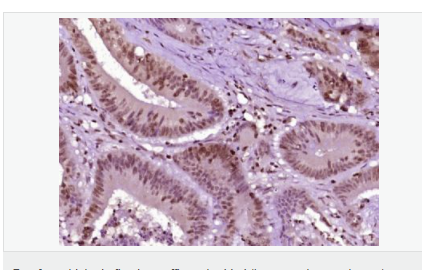

產品應用WB=1:500-2000 ELISA=1:5000-10000 IHC-P=1:100-500 IHC-F=1:100-500 ICC=1:100-500 IF=1:100-500 (石蠟切片需做抗原修復)

image.png